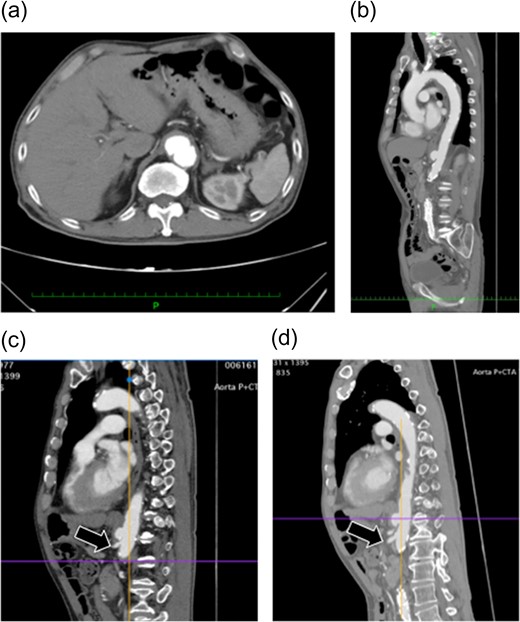

Preoperative enhanced computed tomography. (a and b) A saccular aneurysm can be observed on the descending aorta. (c) The aneurysm is very close to the celiac artery (arrow: origin of the celiac artery). The length of the celiac trunk is 11 mm. (d) The distance to the SMA is 21 mm (arrow: origin of the SMA). No endoleaks were noted in the aneurysm.